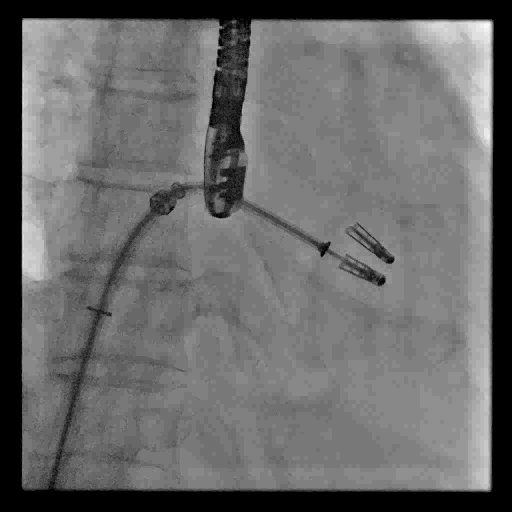

视频2 经食道超声心动图引导穿刺房间隔

4月11日上午患者在全麻下接受MitraClip经皮二尖瓣夹合术。术中穿刺右股静脉,经食道超声心动图(TEE)再次评估瓣膜病变(视频1),并引导顺利穿刺房间隔(视频2)。随后送入二尖瓣夹合系统,在TEE引导下于二尖瓣P2区植入MitraClip XTR夹合器一枚(视频3),二尖瓣关闭不全减轻,但夹合器内侧仍存在反流(视频4)。团队决定为患者植入第二枚夹合器(MitraClip NTR),手术过程顺利(视频5)。TEE三维显示在植入第二枚NTR夹合器后,二尖瓣呈双孔启闭,两枚夹合器位置、结构正常(视频6)。配备心腔镜功能的TEE三维TrueVue彩色多普勒显示二尖瓣反流将至少量(视频7),且未致二尖瓣口狭窄(图1),夹合效果满意。手术通过视频连线得到香港亚洲心脏病中心主任林逸贤教授的技术支持。